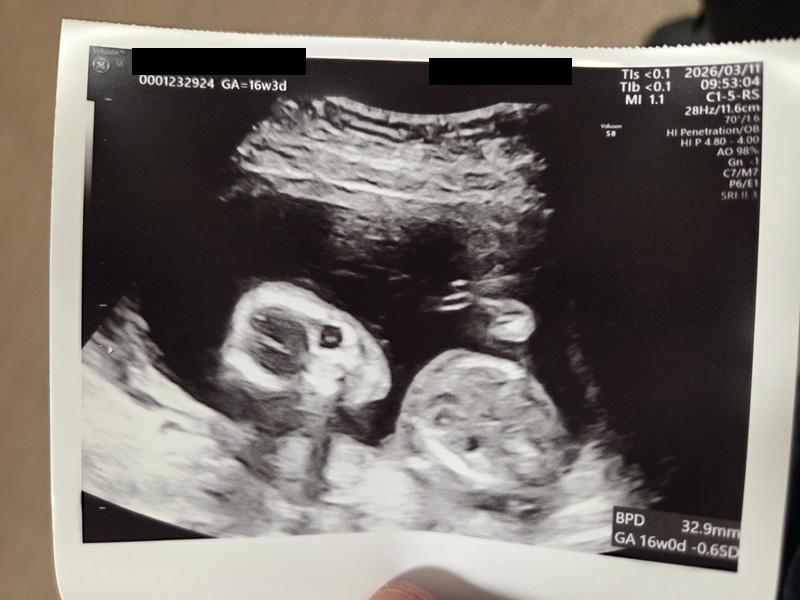

この度私は妊娠した事をご報告します。現在16週(6か月)です。子供は籍入れた後追々欲しいなと思っていましたがまさかの順番が・・・でしたが今年籍を入れることになりました。この二つが今回の報告となります。